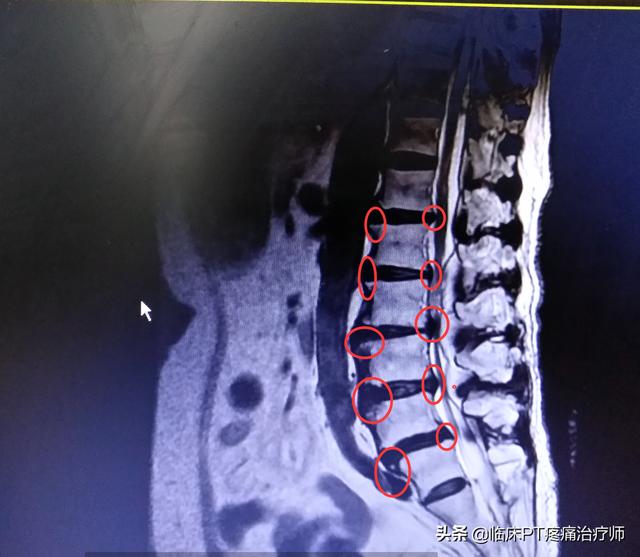

ただ横になっていればいいと思っているはずだが、実はそうではなく、下の写真のように、五点潜在アーチ橋の練習をアップにして、腰や背中の筋肉や靭帯をストレッチして鍛え、その3ヶ月で、腹筋も出す!